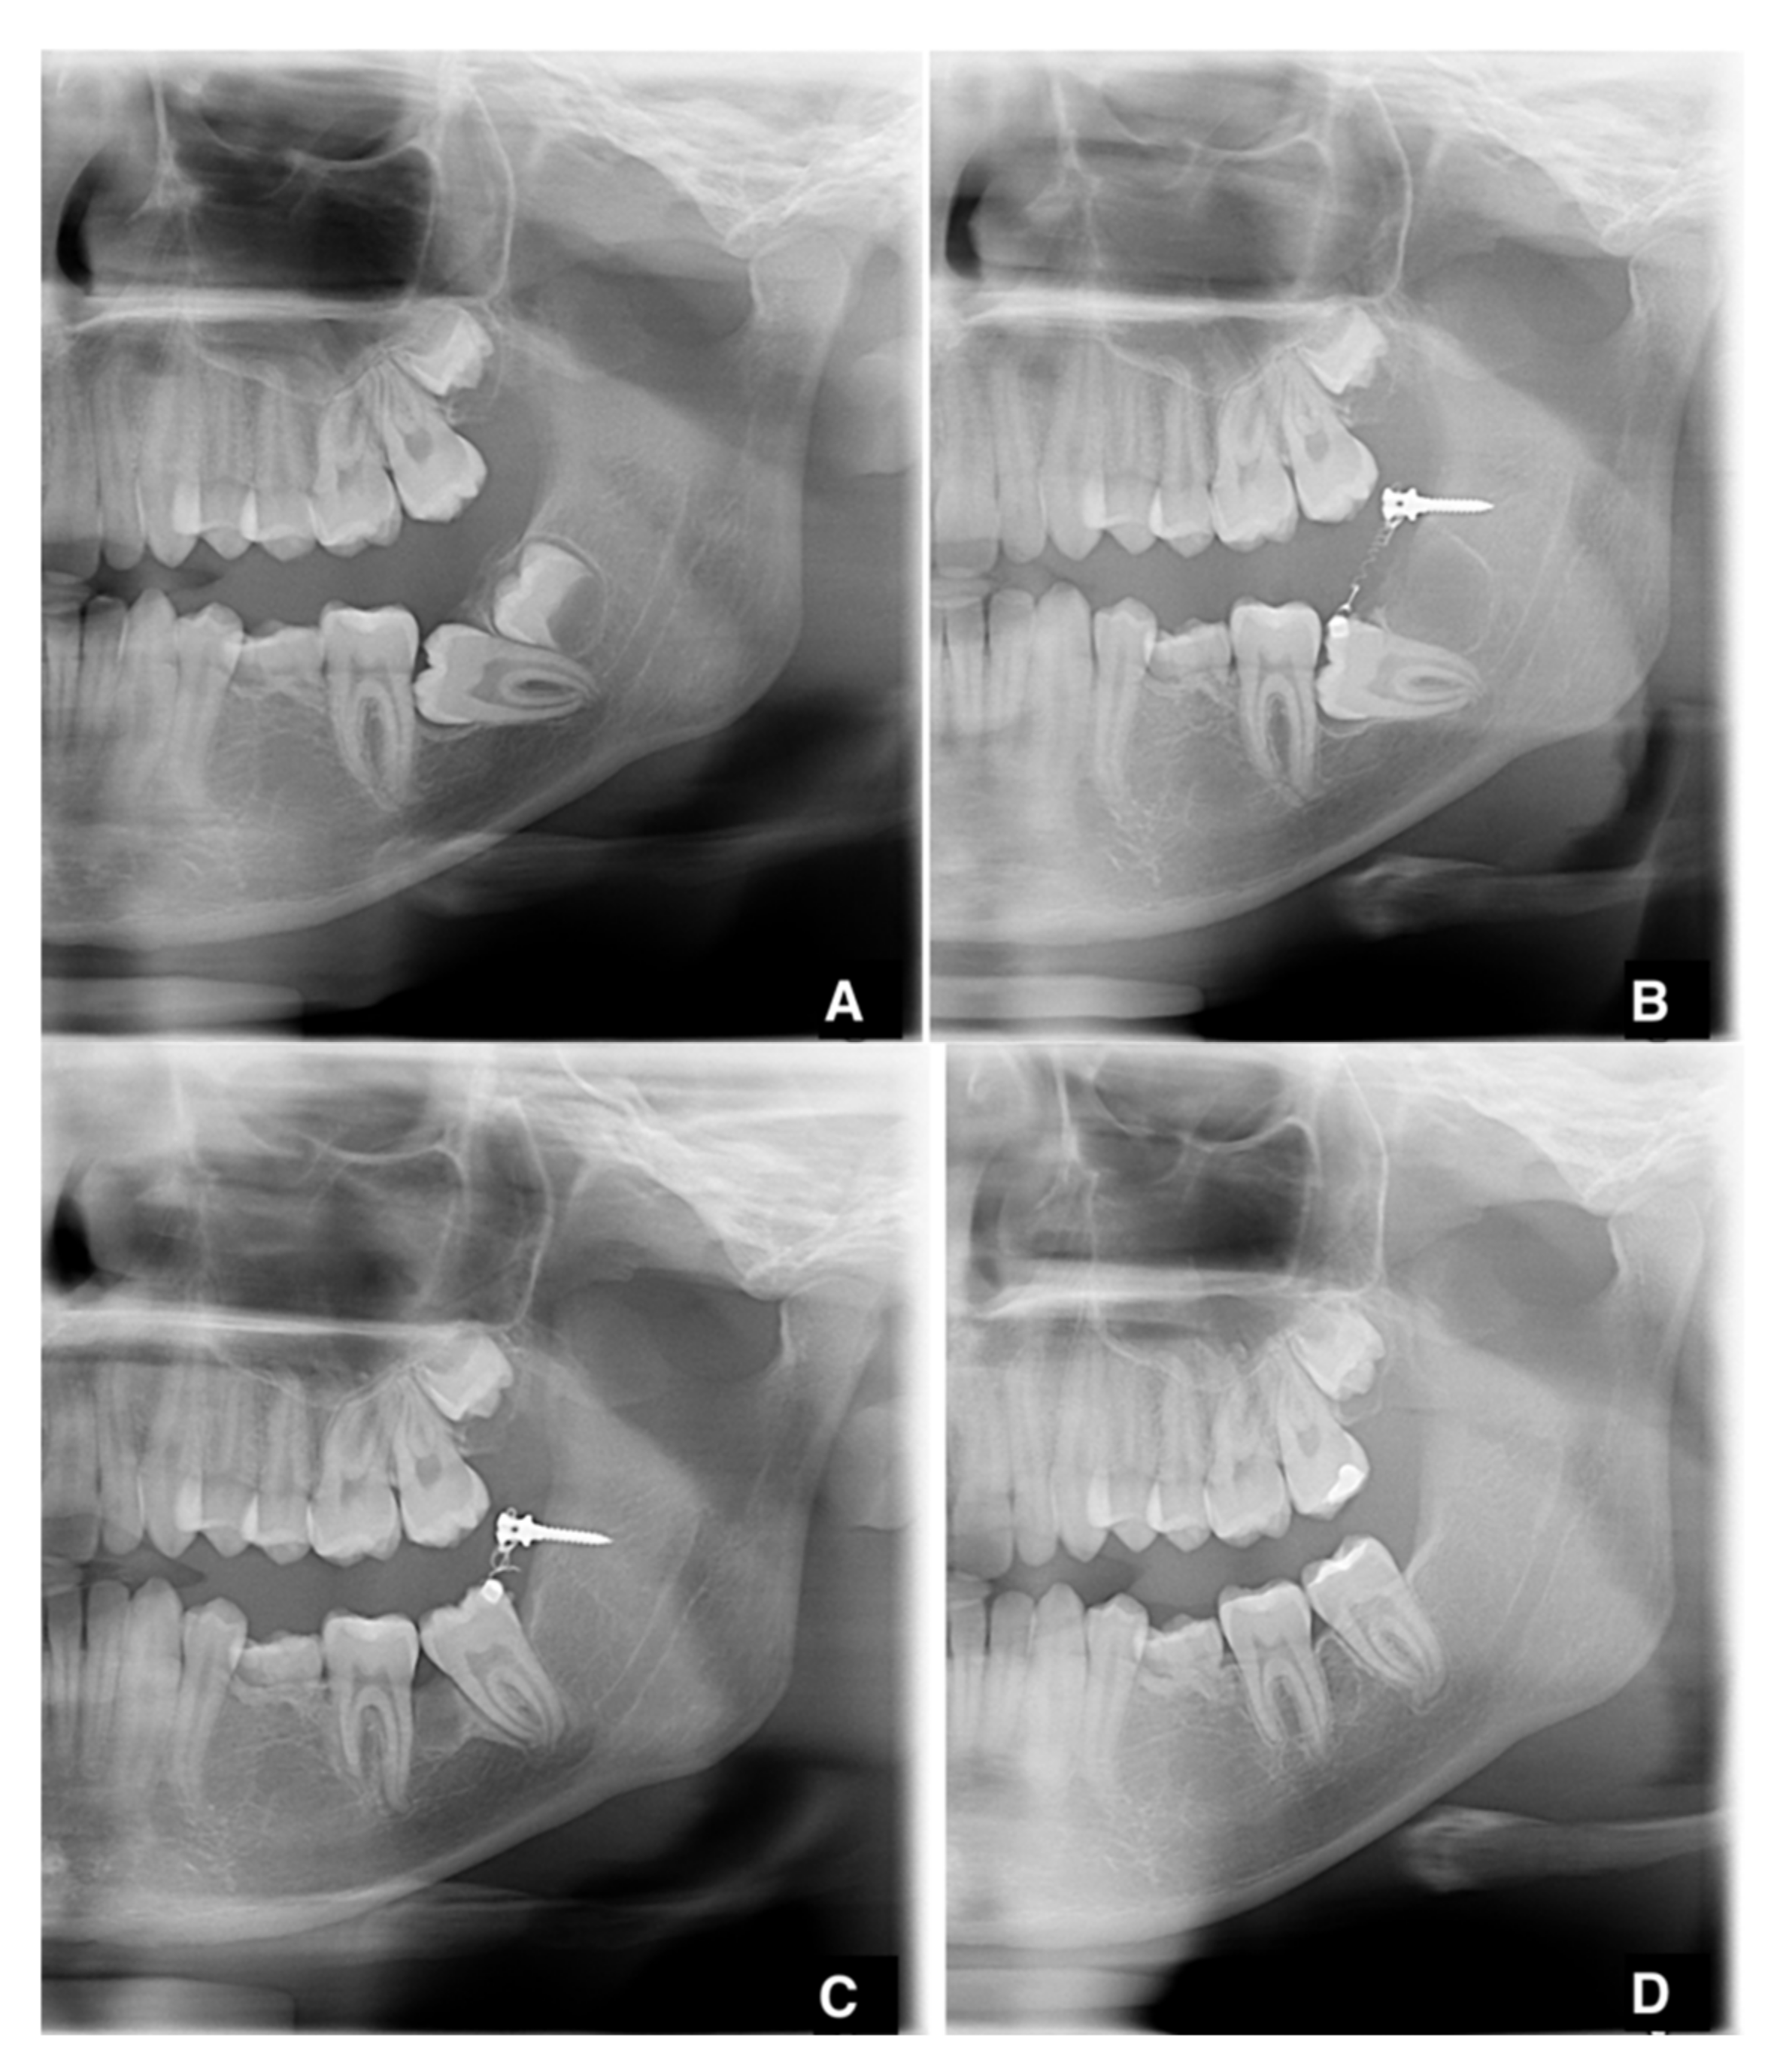

2.2. Surgical and Orthodontic Procedures

2.3. Measurements

3. Results